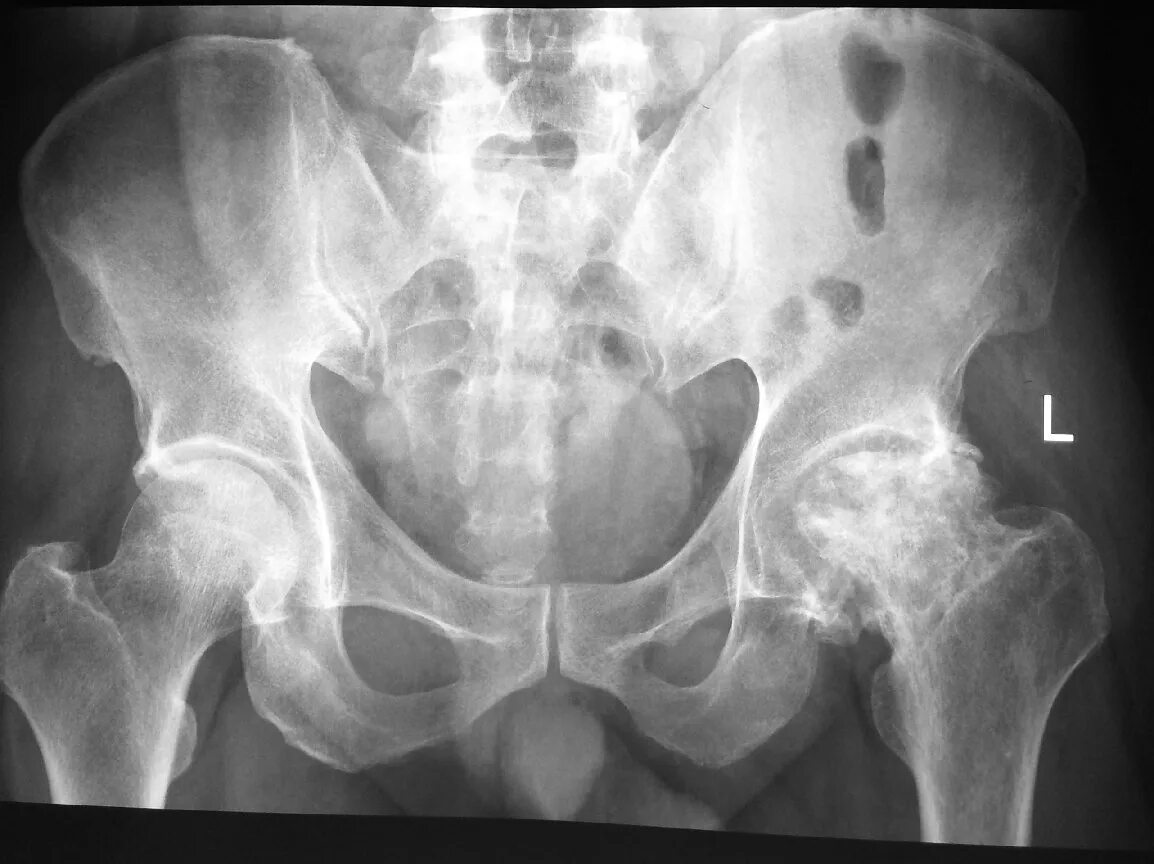

Разрыв крестцово подвздошного сочленения